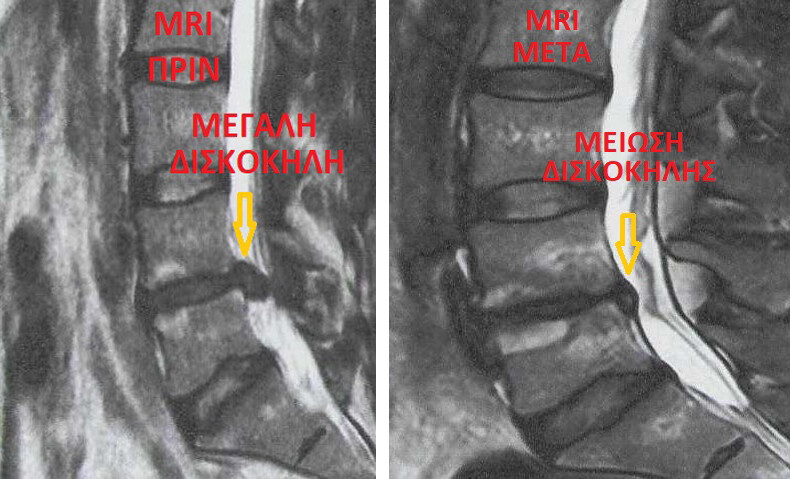

Ο Ορθοπαιδικός Χειρουργός Σπονδυλικής Στήλης Μπενάρδος Νικόλαος με τη δημιουργία της MISS - Μπενάρδος είναι από τους πρωτεργάτες στην καθιέρωση στην Ελλάδα, της ρομποτικής χειρουργικής σπονδυλικής στήλης (2008 1η ρομποτική διαδερμική σπονδυλοδεσία στην Ελλάδα), ενδοσκοπικής χειρουργικής σπονδυλικής στήλης (2009 1η ενδοσκοπική δισκεκτομή ομάδας MISS - Μπενάρδος) και δισκοπλαστικής με έγχυση ενδοδισκικού τζελ (discogel)

Δισκοπλαστική (Discogel, RF)